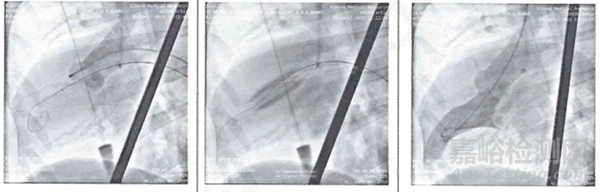

如下圖所示,在動物實驗中,RunFlow的擴張效果良好,其中空結(jié)構(gòu)使球囊在充盈狀態(tài)下仍有血流通過。

RunFlow®的空腔結(jié)構(gòu)使心臟血液能夠通過開放的中央管腔連續(xù)流動,從而在術(shù)中保持穩(wěn)定的脈壓水平。對于心功能儲備較低的患者來說,避免球囊擴張過程完全堵塞左心室流出道,降低室顫、心臟驟停等嚴(yán)重并發(fā)癥的出現(xiàn)具有重要意義。